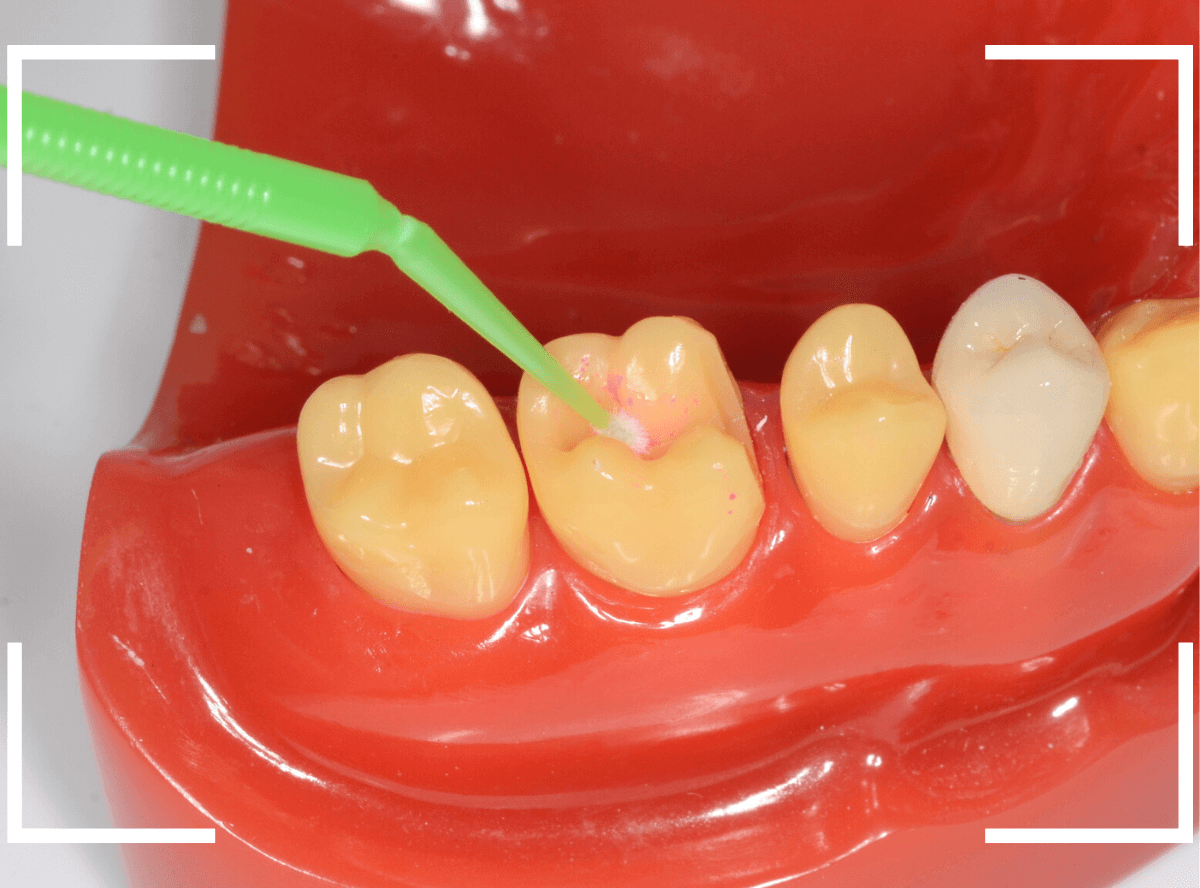

う蝕検知液

う蝕検知液は、虫歯を除去した部分に滴下して使います。

滴下した部分を水洗・乾燥して、染色されている部分は虫歯の取り残しあり、と判断します。

実際に使っている場面です。

実際の検知液を使い方です。

ノズルをう蝕部に直接挿入して使うのが一般的ですが、それですとノズルの先端が汚染されてしまいます。

という事で、当院では使い捨てのアプリケーターを使い、ノズルが歯に直接触らないようにして使用しています。